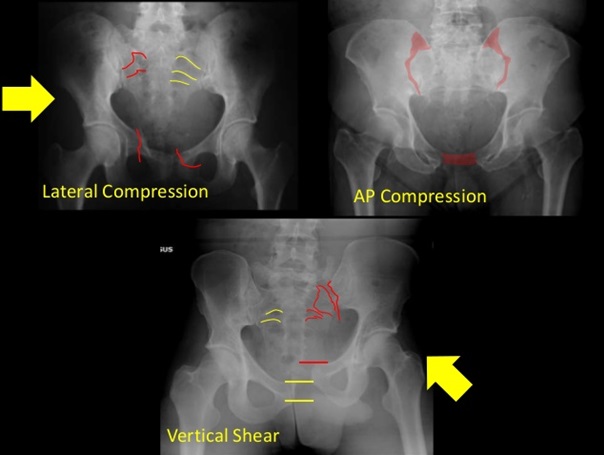

범이는 어느 날 구조대원의 집 근처에 나타난 아이로, 그 이후로 몇 년째 먹이를 주고 있다고 한다. 그러나 1월 2일, 범이는 움직이지 못하고 울기만 하여 구조대원이신 허 할머니가 구조되셨다고 하시고 돌아오셨고, 이후 다른 병원에서 엑스레이 촬영을 하셨고 골반 골절 진단을 받으셨습니다. 골반 골절로 병원에 내원 교통사고가 의심됩니다.

의사를 방문했을 때 아이의 상태는 (1) 오른쪽 골반 천장 관절 탈구 (1-2) 오른쪽 골반 비구 골절 (2) 왼쪽 장골 날개 골반 뼈) 골절 (2-1) 왼쪽 골반 뼈 비구 골절이었습니다.

따라서 수술 계획은 다음과 같습니다! (1) 천장관절 탈구 오른쪽 골반의 탈구 – 원래는 골반에 가해지는 부하를 줄이기 위해 긴 나사로 탈구를 고정한 후 오른쪽 고관절 절제술을 시행해야 했지만 – 보호자분의 스플릿 상담 후 , 고관절 절제술 만하고 예후를 관찰하기로 결정했습니다. – 골반의 무게를 줄이면 자연스럽게 치유될 가능성이 있기 때문입니다. (1-2) 오른쪽 골반뼈 비구의 골절. , 비구 골절은 별도의 수술이 필요하지 않다고 판단한다. (2) 왼쪽 골반뼈의 장골날개 골절 – X-ray상 2조각의 골절 소견.